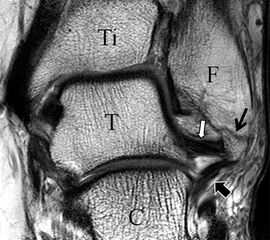

Jedoch findet man sich auch hier mit dem Problem der in den Standard-Projektionen schräg verlaufenden Syndesmose konfrontiert. Der oligofaszikuläre Aspekt der vorderen Syndesmose kann in der axialen Schnittebene eine zum Verwechseln ähnliche Morphologie wie eine Ruptur aufweisen (Abb. 15 b und c). Doppelangulierte Schnitte entlang der Achse (schräg koronar/schräg sagittal) lassen hingegen eine eindeutige Beurteilung der Bandstrukturen zu (Abb. 16) und verbessern die Syndesmosendiagnostik.

Bezogen auf die Transversalebene verläuft die Syndesmose ca. 30° schräg cranio-caudal anguliert (Abb. 15 a). Häufig lassen sich drei Hauptfaszikel differenzieren: das kürzeste superiore, das stärkste mittlere und das längste kaudale Faserbündel. Ein akzessorisches Bündel, das anteriore-inferiore, tibiofibulare Ligament (AITFL) oder auch Bassett-Ligament wird in 80-94% der Patienten nachgewiesen 8. Dies weist einen unmittelbaren Bezug zur anterolateralen Talusschulter auf (Abb. 17). In Kombination mit einer Außenbandinstabilität und konsekutivem, talarem Vorschub kann dieses zu einem Impingement an der anterolateralen Taluskante führen mit nachfolgender chondraler oder osteochondraler Läsion.